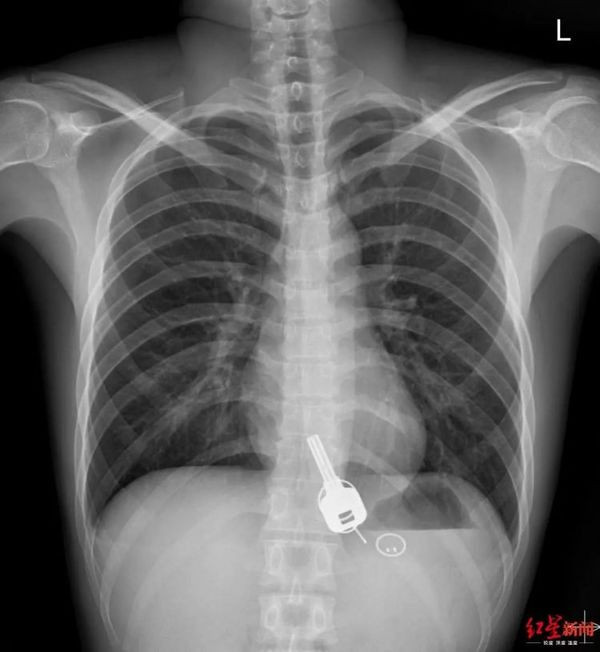

Khi chụp X-quang cho Chang, bác sĩ sốc khi thấy một vật trong giống chiếc chìa khóa trong thực quản của nam thanh niên. Khi hỏi Chang, anh này thừa nhận làm mất chìa khóa nhà vào đêm hôm trước nhưng không thể giải thích vì sao vật này lại ở bên trong cơ thể mình.

Chiếc chìa khóa nằm trong cơ thể của bệnh nhân Chang theo ảnh chụp X- quang. Ảnh: Sohu.

Theo tờ Sohu, Chang vô cùng bất ngờ trước sự việc. Nhân viên tại Bệnh viện Đông Quan đã phân tích tình hình và quyết định can thiệp bằng thủ thuật để đưa chìa khóa ra khỏi hệ thống tiêu hóa của Chang bởi nếu để vật này “chui khỏi” cơ thể bệnh nhân một cách tự nhiên sẽ đem lại rủi ro vì vật cứng có thể làm rách ruột hoặc gây tắc nghẽn đường ruột, đe dọa đến tính mạng. Còn trong trường hợp cố đưa chìa khóa ra khỏi cơ thể bằng thiết bị nội soi có thể làm vỡ thực quản của bệnh nhân. Lựa chọn thứ ba là phẫu thuật khẩn cấp.

Bác sĩ Zhang Yuyu phụ trách ca của Chang nói với phóng viên rằng ban đầu họ thử lấy chìa khóa bằng máy nội soi dạ dày nhưng có một rắc rối khi vật thể không lọt qua phần hẹp nhất ở thực quản của bệnh nhân. Chìa khóa có kích thước lớn và việc kéo mạnh có thể làm rách thực quản, gây ra hậu quả khó lường. Do đó, bác sĩ đã dừng phương án này.

Sau khi gây mê, các bác sĩ tiêm thuốc giãn cơ bắp cho Chang và sau đó bác sĩ tiêu hóa có thể đưa chìa khóa và móc khóa bằng nhựa ra khỏi thực quản của bệnh nhân.

Chiếc chìa khóa cuối cùng đã được lấy ra khỏi cơ thể Chang một cách thành công nhưng làm thế nào mà anh này lại nuốt chìa khóa vào bụng vẫn là bí ẩn vì anh chàng nói không nhớ bất cứ chuyện gì đã xảy ra vào đêm say rượu.